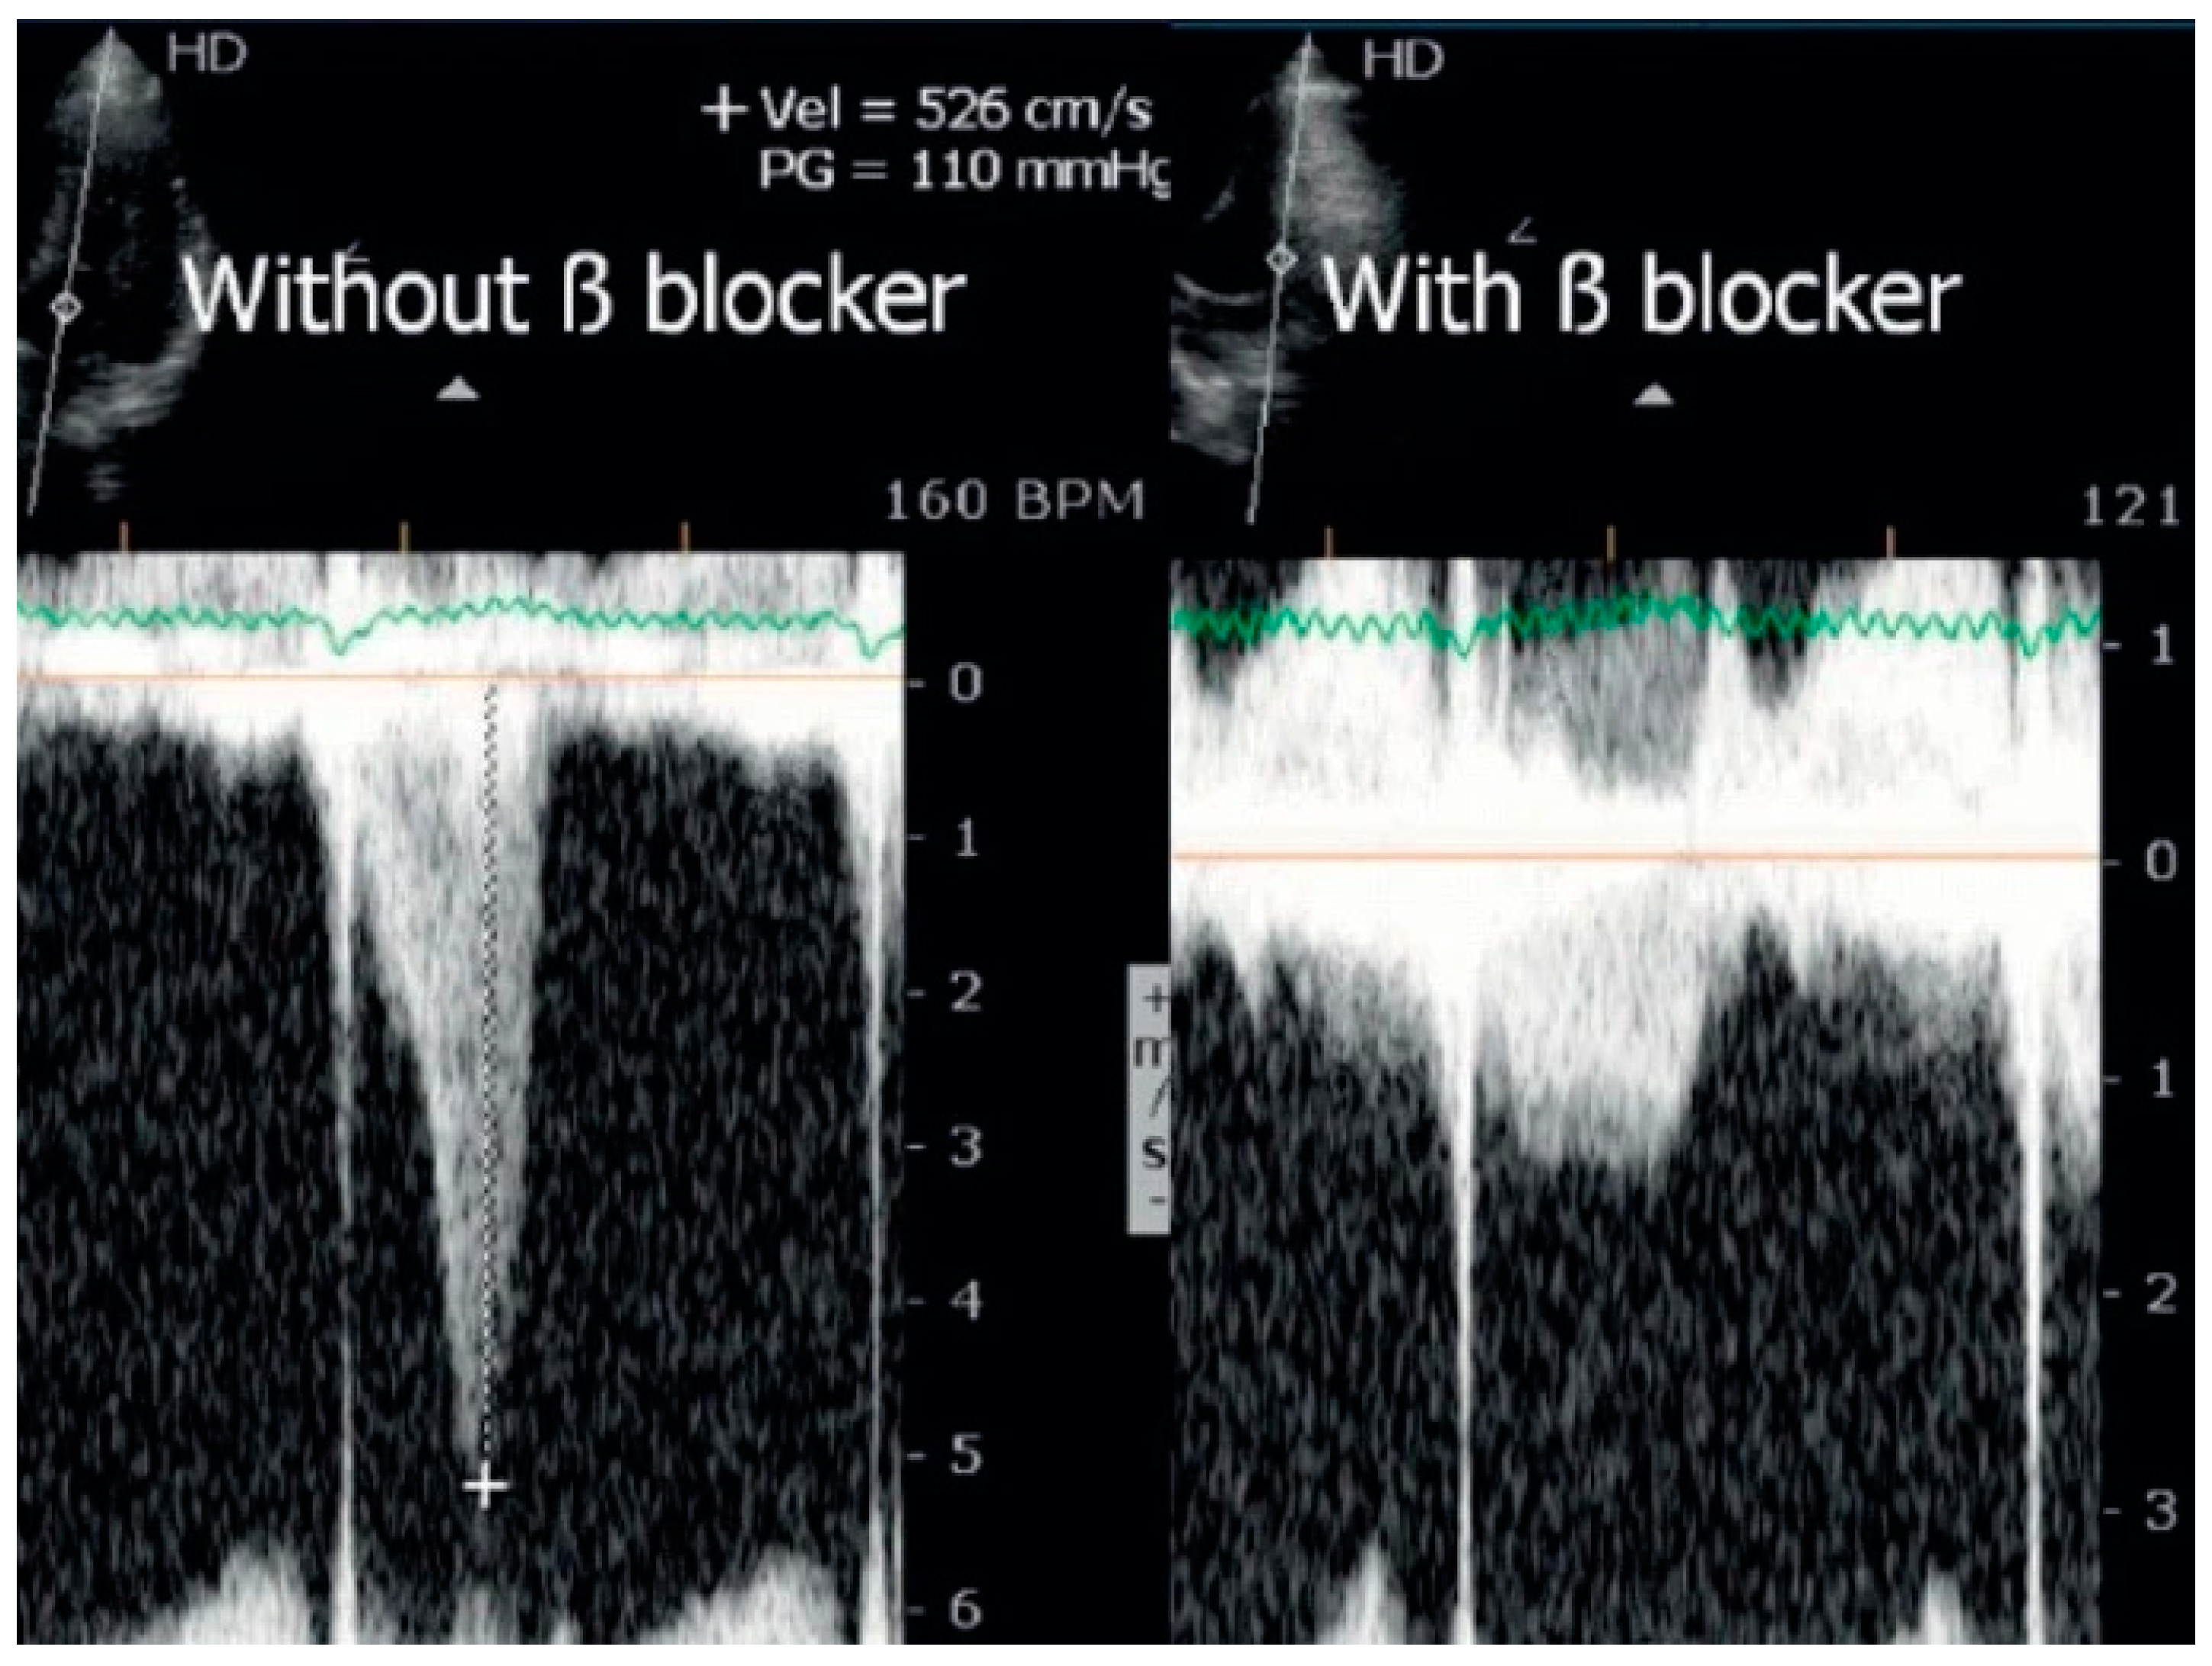

- Cabrera-Bueno, F.; García-Pinilla, J.M.; Gómez-Doblas, J.J.; Montiel-Trujillo, A.; Rodríguez-Bailón, I.; de Teresa-Galván, E. Beta-blocker therapy for dynamic left ventricular outflow tract obstruction induced by exercise. Int. J. Cardiol. 2007, 117, 222–226. [Google Scholar] [CrossRef] [PubMed]

- Cotrim, C.; Lopes, L.R.; Almeida, A.R.; Miranda, R.; Ana, A.G.; Cotrim, H.; Andrade, J.P.; Picano, E.; Carrageta, M. Efficacy of beta-blocker therapy in symptomatic athletes with exercise-induced intra-ventricular gradients. Cardiovasc. Ultrasound. 2010, 8, 38. [Google Scholar] [CrossRef] [PubMed]

- Cabrera Bueno, F.; Rodríguez Bailón, I.; López Salguero, R.; Doblas, J.J.G.; Cabeza, A.P.; Hernández, J.P.; Franco, A.D.; Hidalgo, L.M.; de Teresa Galván, E. Obstrucción dinámica intraventricular izquierda inducida por esfuerzo [Dynamic left ventricular outflow tract obstruction induced by exercise]. Rev. Esp. Cardiol. 2004, 57, 1179–1187. [Google Scholar] [CrossRef] [PubMed]